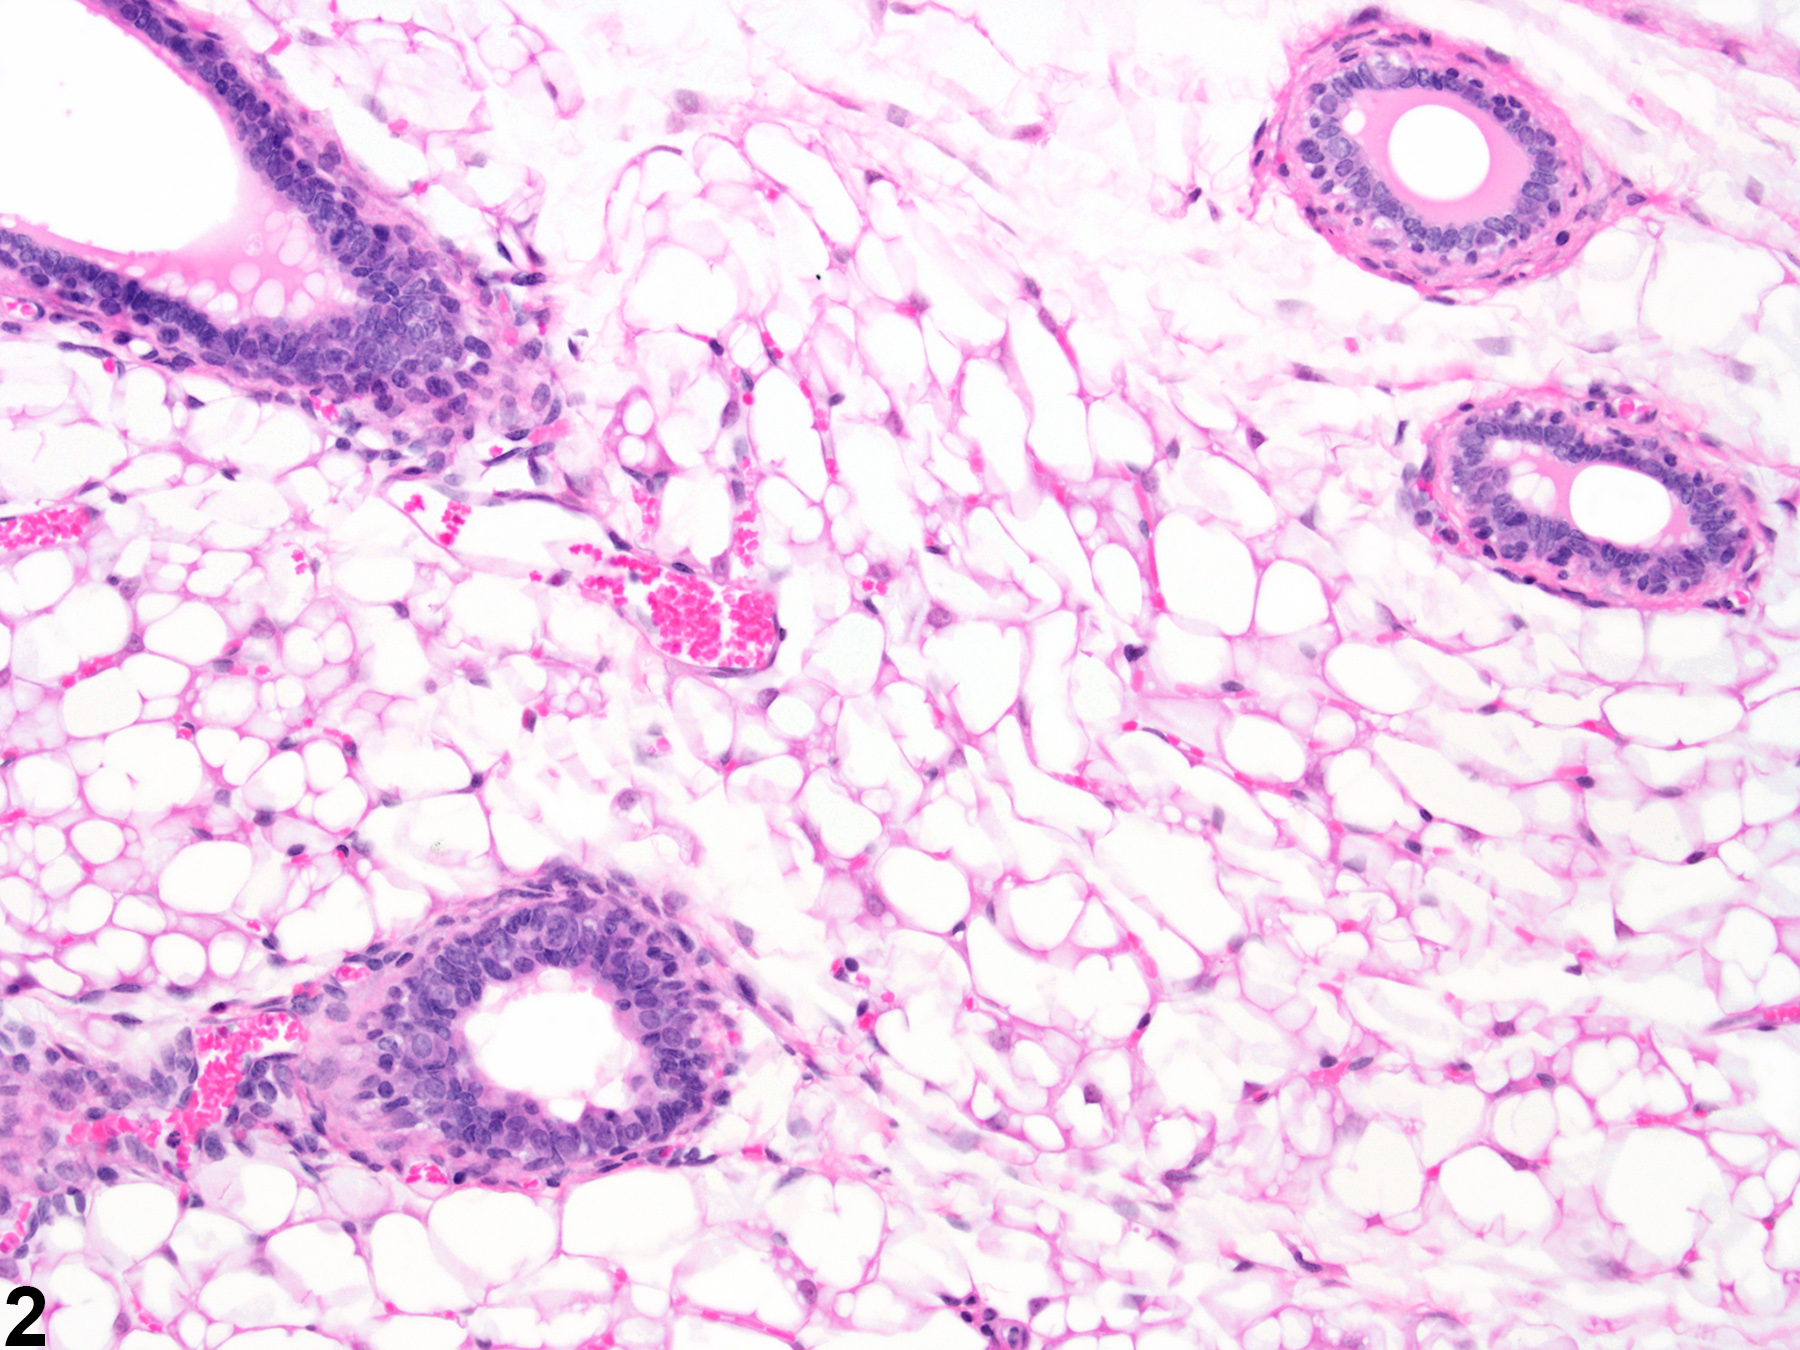

Diffuse atrophy of the normal alveolar (acinar) (Figure 1, Figure 2, Figure 3, and Figure 4) and ductular (Figure 3 and Figure 4) tissue of the mammary gland of rats and mice is an uncommon finding. It is most often associated with compound administration. Involution of the mammary gland begins in the second year of life in rats and mice and is characterized by loss of distal ducts in mice, and regression of terminal end buds and decrease in size of lobules in rats. This change, of course, would be present in both treated and control animals. Treatment with certain xenobiotics for long periods can induce hormonal perturbations, such as hypoestrogenism or estrogen receptor (ER) antagonism in rats that causes atrophy of the female mammary gland. With atrophy of the female mammary glands, the ductular and acinar components are both affected, resulting in a prominent appearance of the mammary gland fat pad. The epithelial cells lining the affected ducts and acini are low cuboidal and have a high nuclear cytoplasmic ratio. The term feminization refers to the conversion of the normally lobuloalveolar pattern of male rat mammary glands to the tubuloalveolar pattern seen in female rats and thus differs slightly from atrophy. Tamoxifen and toremifene are selective estrogen receptor modulators (SERM) and are examples of potent estrogen receptor antagonists in the rat mammary gland that cause ductal atrophy (and ectasia) in females and acinar atrophy in males. Care must be taken during tissue sectioning to prevent the erroneous appearance of atrophy during histopathologic evaluation.

Mammary gland - Normal in a female B6C3F1/N mouse from an acute study. Normal mammary gland with well-developed mammary fat (adipose) pad and age appropriate ductular and acinar tissue.